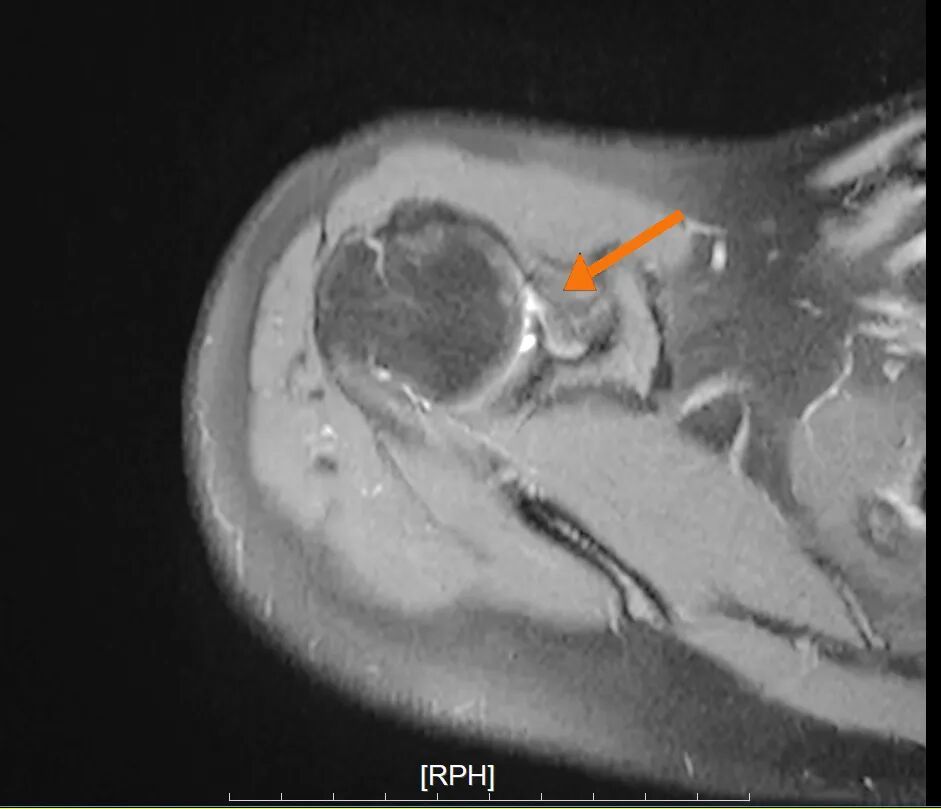

肩关节前盂唇撕裂

针对林女士的病情,叶庭均与安亭医院骨科团队制定了关节镜微创手术方案。该手术仅需在肩部开数个不足1厘米的小切口,通过内置摄像头与精密器械精准修复受损部位,具有创伤小、恢复快的优势。手术中,医生发现其肩关节前盂唇存在明显撕裂,并伴有肱骨头骨缺损,随即进行了盂唇修复与关节囊固定术,重建了肩关节稳定性。术后,林女士在骨科团队指导下逐步进行康复训练,肩关节功能恢复顺利,目前已重返日常生活。